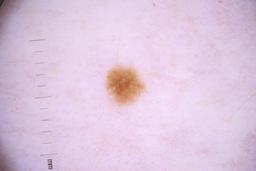

ISIC_4077341

- Challenge 2020: Training

- IP_1969685 IL_9238622

Clinical

| Field | Value |

|---|---|

| acquisition_day | 1 |

| age_approx | 50 |

| anatom_site_1 | Trunk |

| anatom_site_2 | Anterior trunk |

| concomitant_biopsy | False |

| dermoscopic_type | contact non-polarized |

| diagnosis_1 | Benign |

| diagnosis_confirm_type | serial imaging showing no change |

| family_hx_mm | False |

| image_type | dermoscopic |

| lesion_id | IL_9238622 |

| patient_id | IP_1969685 |

| personal_hx_mm | True |

| sex | male |